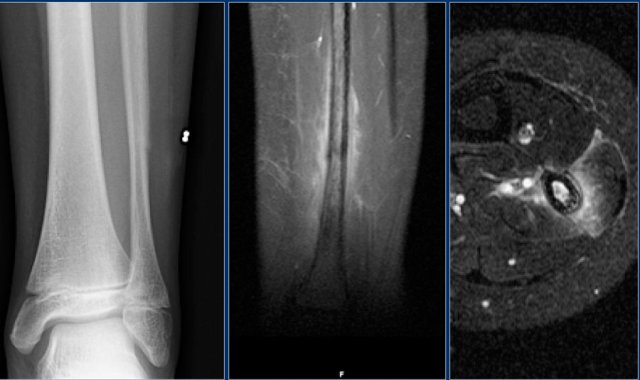

Here images of an osteosarcoma in the right femur.

It is barely visible within the bone, but an agressive periostitis is seen (arrow).

Continue with the MR-images.

The sagittal T1WI and Gd-enhanced T1W-image with fatsat show a large tumor mass infiltrating a large portion of the distal femur and extending through the cortex into the soft tissues.

Here an example of a patient with a stress fracture of the distal fibula.

Coronal MR image demonstrates subtle low intensity line representing the fracture.

Differential diagnosis based on the periosteal reaction and the extensive edema:

• Osteomyelitis

• Eosinophilic granuloma